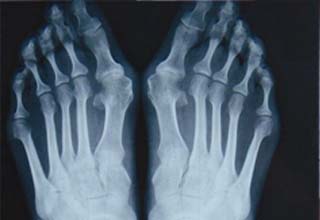

拇指外翻作为一种疾病,虽然早期除了外观不美丽、选鞋困难及容易损坏鞋形,还没有给人们带来太多的不适症状。但是随着年龄增长,拇外翻畸形程度的加重,会产生很多严重的并发症,如拇…「查看详情」

大脚骨病怎么治疗对患者更好?大脚骨的出现不仅会给我们的身体造成伤害,同时还会给患者日常生活带来极大的不便和影响,生活中还会受到其他人的歧视,给患者的生理和心理上造成很大的…「查看详情」

怎样治疗拇指外翻?拇指外翻不仅脚形难看,穿鞋变形,还可能会伴有拇囊炎,疼痛,并发脚垫、鸡眼、爪形趾等脚趾畸形。所以,大脚骨一旦形成,需及时进行有效治疗。怎样治疗拇外翻成为…「查看详情」